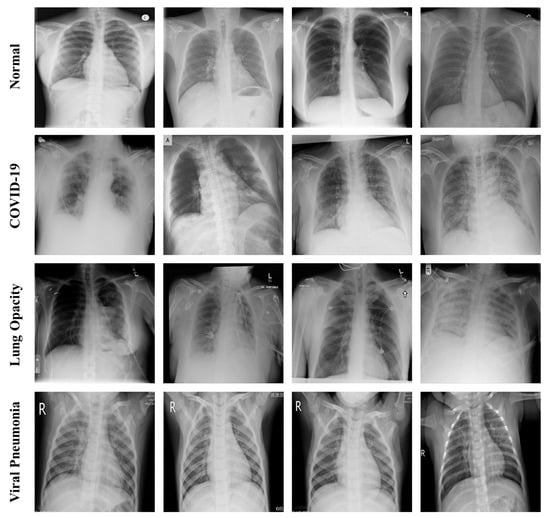

3. COVID-19 Dataset

The COVID-19 dataset included images published by Kaggle [19,39,40]. The data points were categorized into four classes: normal, COVID-19, lung opacity, and viral pneumonia. Each class was created by merging several previously published data sets. The normal data points comprised 8851 images from the Radiological Society of North America (RSNA) [41] and 1341 images from Kaggle’s chest X-ray images (pneumonia) [42]. The total number of images for COVID-19 was 3616, and each image was from the BIMCV-COVID19 dataset, Germany Medical School, Italian Society of Medical Radiology (SIRM), Github, Kaggle, Twitter, and the COVID-19 CXR repository [43,44,45,46,47,48,49,50,51]. The lung opacity data comprised 6012 CXR images acquired from the RSNA. The number of viral pneumonia data points was 1345 and they were obtained from CXR images (pneumonia). The CXR images of the dataset were in grayscale. The resolution of each image was 299 × 299 pixels and the image format was portable network graphics. Figure 2 shows the sample images for each class. Table 1 presents the number of images in each class.

Figure 2. Sample CXR images for each dataset.